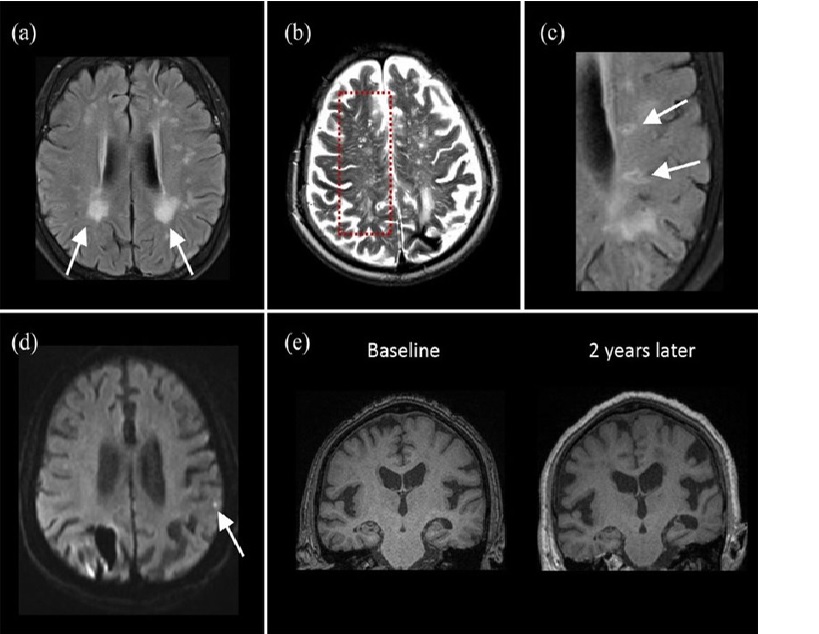

Ischemic presentations in cerebral amyloid angiopathy. (a) T2-FLAIR MRI shows white matter hyperintensities with posterior predominant pattern (arrows). (b) MRI-visible perivascular spaces located at centrum semiovale are depicted on T2-weighted MRI as hyperintense signals with linear or dotlike appearance. (c) T2-FLAIR MRI shows ovoid lesions with hyperintense rim at periventricular areas, suggestive of lacunar infarcts. (d) High resolution diffusion-weighted imaging study shows a hyperintense dot in the cortical region, indicative of cortical microinfarct. (e) Progressive brain volume loss is shown on longitudinal follow up of T1-MRI studies in 2 years. FLAIR, fluid-attenuated inversion recovery; MRI, magnetic resonance imaging.